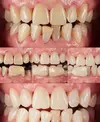

تطبيقات الزيركونيوم

تطبيقات البورسلان

القشور الخزفية (Laminate veneer)